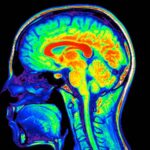

Stem Cell Therapies Could Treat Parkinson’s Disease by Rebuilding Lost Circuitry in the Brain, Studies Suggest

Two small clinical trials tested the safety of injecting stem cells into the brains of Parkinson’s patients and found no […]